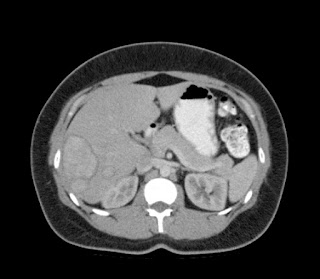

Paciente de 66 años con antecedente de pancreatitis, tomografía control.